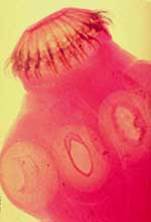

Sán dây dẹt, dài, chia đốt, con trưởng thành sống trong ống tiêu hoá. Sán dây gây bệnh thường gặp: Taenia saginata (sán dây bò), Taenia Solium (sán dây lợn), Echinococcus granulosus, E. Multilocularis, D. Latum, Hymenolepis nana. Con trưởng thành gồm một đầu để bám, một đốt cổ để sinh ra, các đốt và thân (strobila) gồm nhiều đốt (proglottides). Chiều dài thay đổi từ rất nhỏ (3mm) đến dài trên 10m, số đốt thay đổi từ 3 đốt đến 4.000 đốt.

- Phần đầu sán có miệng mang chức năng bám sát vào thành ruột và phần thân có thể sinh thêm các đốt đến khi bám được suốt chiều dài thành ruột.

Đầu sán dây hình quả lê

Mỗi đốt trưởng thành chứa ít nhất là 1 bộ phận sinh dục đực và 1 bộ phận sinh dục cái